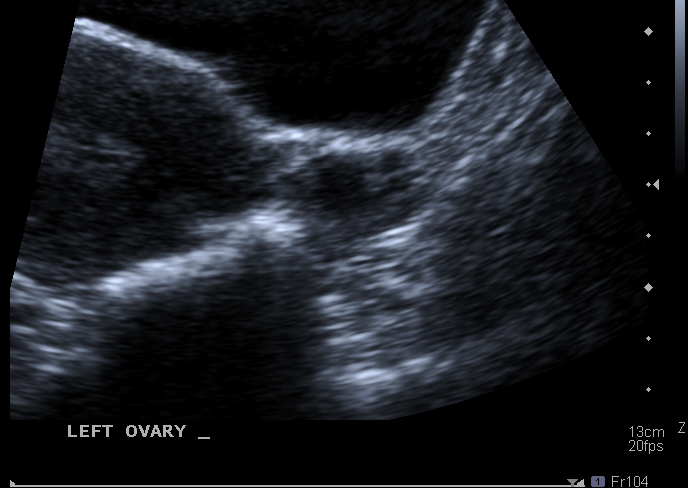

What vascular strcture can the ovaries be shown to be closely related to ?

The R and L external iliac vessels